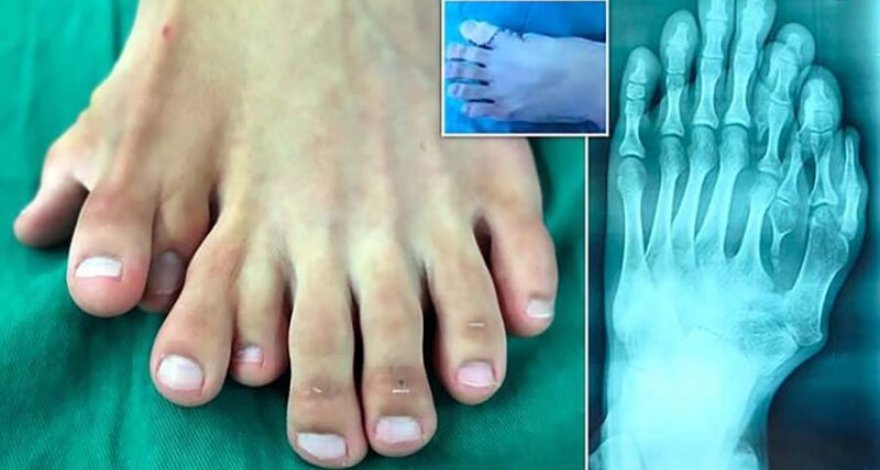

В китайском городе Луфэн, провинция Гуандун, 21-летнему пациенту с девятью пальцами на левой ноге удалили лишние, сообщает Daily Mail.

Повзрослев, китаец все же решил обратиться в больницу. Врачи сделали пациенту рентген и направили на операцию. «Это крайне редкий случай, когда деформацию у человека не исправляли на протяжении 21 года», — подчеркнул доктор У Сян.

Хирурги провели девятичасовую операцию и удалили Ацзюню лишние пальцы на левой ноге. Сейчас пациент находится в больнице и восстанавливается. Ожидается, что его отпустят домой в ближайшие недели. «Я чувствую себя отлично. Хочу сказать большое спасибо доктору Сяну», — заключил китаец.

Полидактилия — одна из самых распространенных наследственных аномалий развития конечностей у людей, собак, котов и лошадей. Лишние пальцы редко являются полноценными, обычно они представляют собой небольшой кусок мягкой ткани.